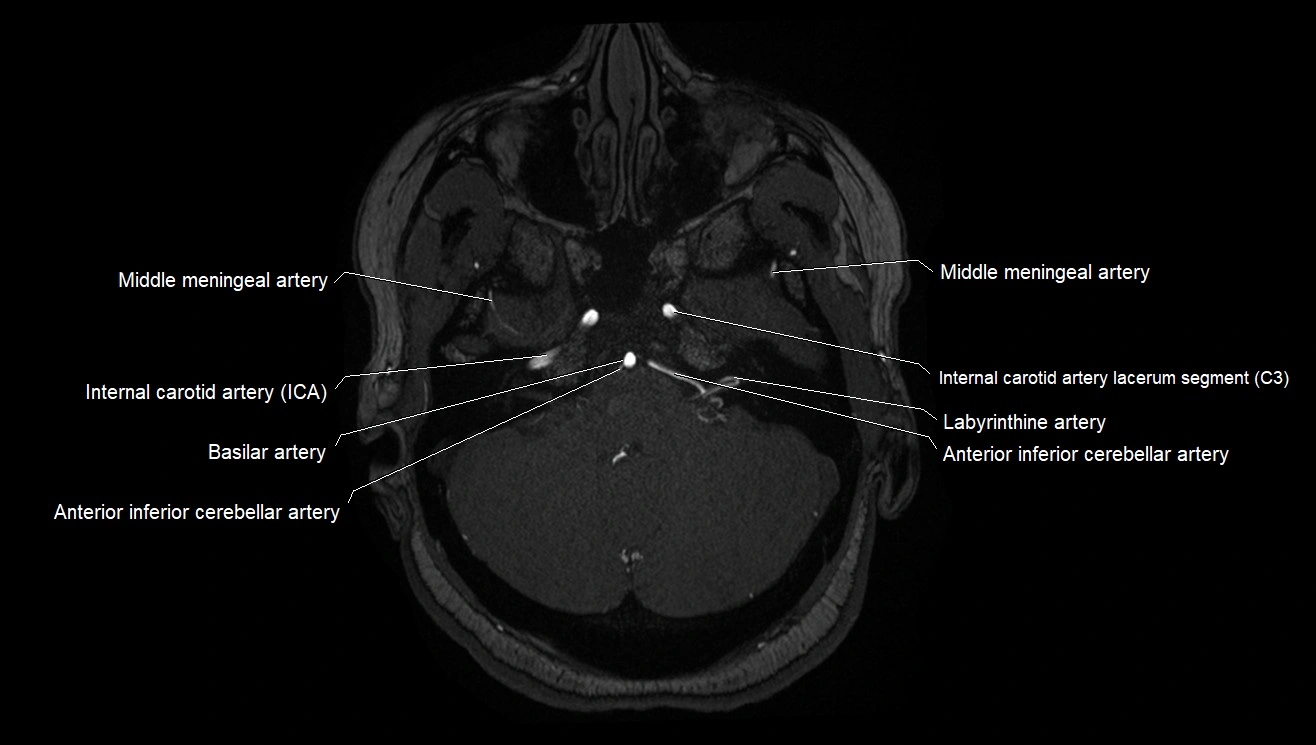

MRA (Magnetic Resonance Angiography):

• Flow-related enhancement makes the AChA appear as a bright, linear vascular signal against suppressed background

• High sensitivity for origin and proximal course; distal branches may be too small to resolve

• Detects stenosis, occlusion, aneurysm, AVM feeders

CTA (CT Angiography):

• Opacified with iodinated contrast, AChA appears as a bright high-attenuation vessel

• Visualized from ICA origin along optic tract toward choroid plexus

• 3D reconstructions depict its course and relation to adjacent arteries

• Gold standard for identifying aneurysms, occlusion, or vascular anomalies